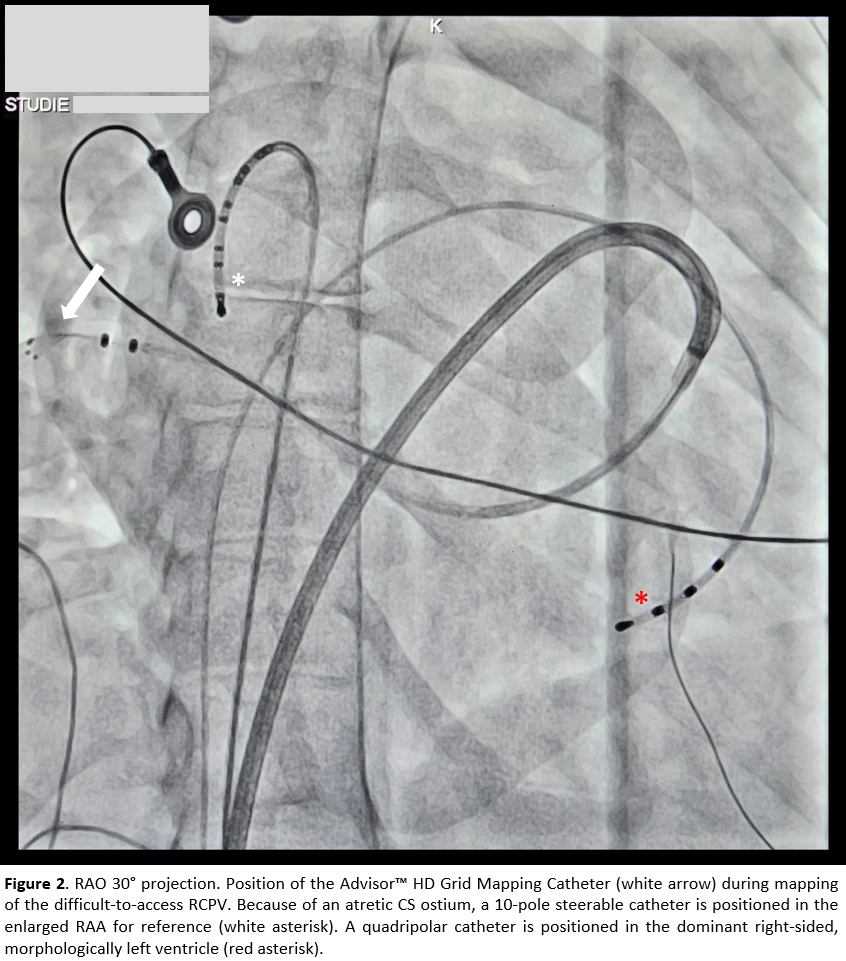

The patient's cardiac anatomy was consistent with a classic DILV featuring a functional single ventricle and ventriculo-arterial discordance. Additional findings included a large atrial septal defect (ASD) with a functional common atrium and a common right pulmonary vein (RCPV). Pre-procedural evaluation comprised an MRI and right-heart catheterization.

Electroanatomic mapping was performed with the EnSite™ NavX™. A significant medial shift of the left atrial sagittal axis was observed, along with a leftward and caudal displacement of the left atrial appendage. In nearly most of the left atrium, endocardial bipolar voltage was <1.5 mV, with only scattered low-voltage areas (LVA) <0.5 mV. The lateral pulmonary veins demonstrated preserved antral conduction, likely reflecting a previously deep balloon position. On the septal aspect, conduction into the RCPV was fully preserved.

Ablation was guided by the Lesion Size Index (LSI) using a TactiFlex™ catheter, with a target LSI of 5.5 along the anterior wall and 5.0 along the posterior wall, resulting in first-pass isolation of all pulmonary veins. Due to the large ASD, maintaining a stable catheter position along the septal line was challenging, allowing for only a ~5-safety margin to the pulmonary veins inferiorly.